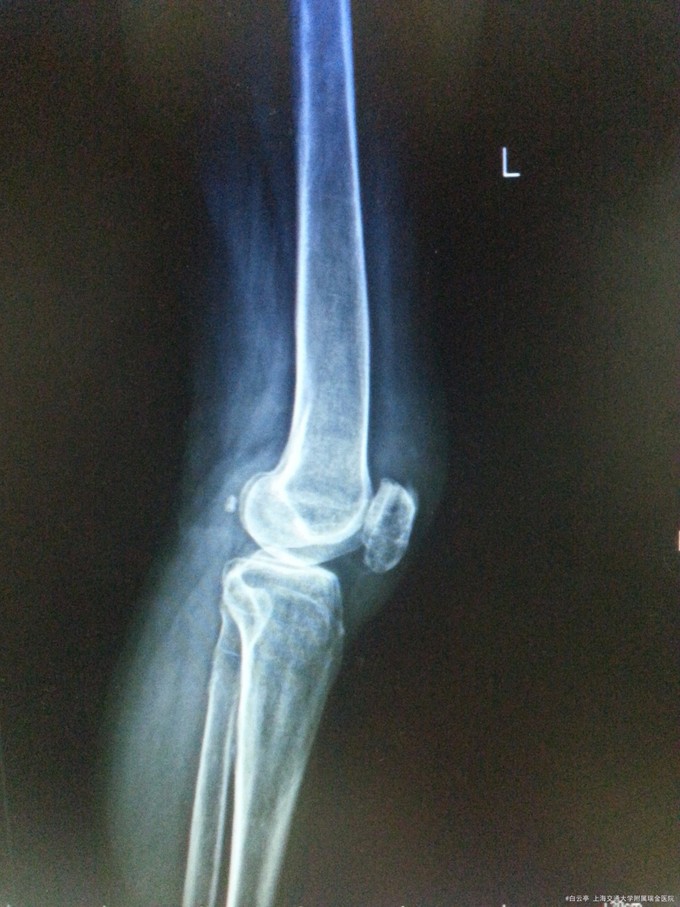

诊断:左髌骨骨折术后取出内固定装置 治疗:入院评估患者骨折恢复可,行“左髌骨骨折术后取出内固定装置”

随访:术后2周患者膝关节手术切口愈合好。活动度及肌力良好 讨论:髌骨张力带术后患者,通常9个月至1年后拔除内固定装置。请讨论各位同道会选择经过多长时间